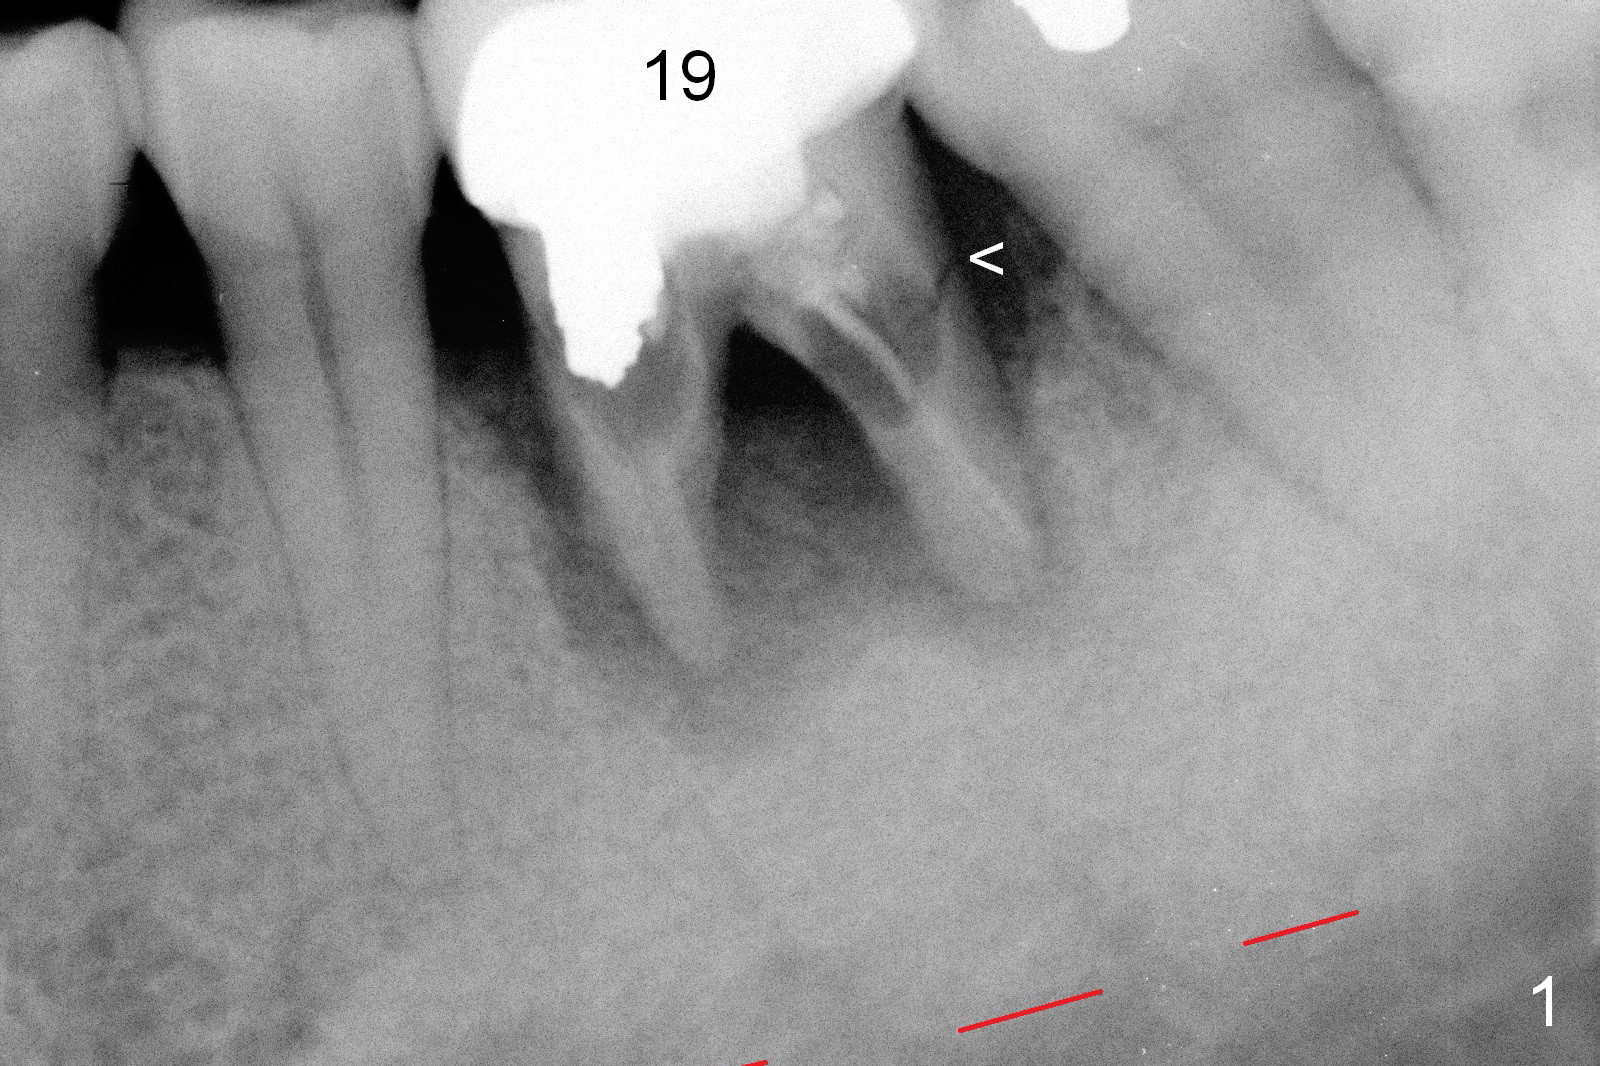

A 37-year-old lady (MP) presents to clinic with chief complaint of bad smell from lower right crown (Fig.1: #19; red dashed line: superior border of the Inferior Alveolar Canal). One of the most prominent pathologies is fracture of the distal root (<). After extraction, the socket is treated with 2% Xylocaine/1:50,000 Epinephrine. The coronal distobuccal plate is defective. Osteotomy is initiated as lingual as possible. The 1st intraop PA shows that the osteotomy is shallow and distal to the almost non-existent septum (Fig.2 S). The osteotomy is intended to move more mesially, but the result is not obvious when 4.5x14 mm drill is in place (Fig.3 D). The depth of the osteotomy is increased by 3 mm; a 5x17 mm tap is stable (Fig.4 T). A 5x12 mm implant (Fig.5 I) is placed until it cannot be turned. The implant is higher than the distal crest (^). In addition there is space apical to the implant (Fig.5*). After 5 mm drill is used, the implant is seated deeper with insertion torque < 35 Ncm (Fig.6). It suggests overprep. Anyway, an immediate provisional is fabricated after placement of an abutment (A). After reline, the provisional fits well. It has to be removed with forceps for occlusal adjustment. Finally the abutment/implant complex turns in the socket with fingers. The rotation/position of the complex is randomly adjusted. When the provisional is cemented, it does not seat completely, but is stable. If the implant osteointegrates, the provisional must play a role in stabilizing the implant. Bone graft is placed in the gap prior to cementation (Fig.6 *).